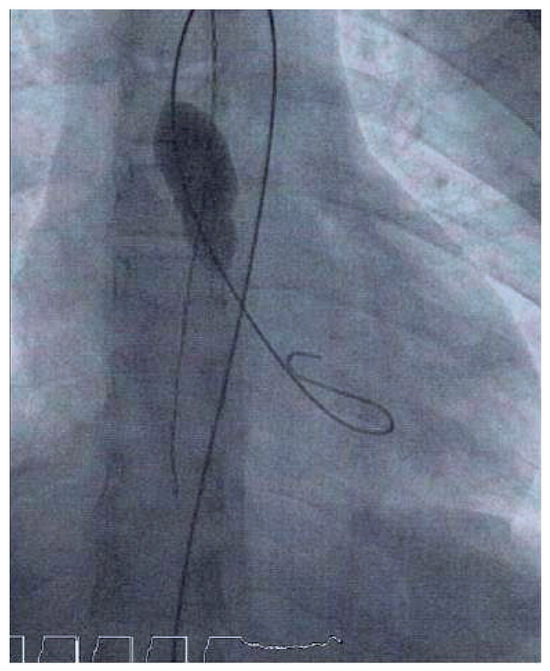

Case report